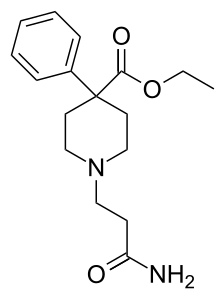

The first fully synthetic opioid was meperidine (later demerol), found serendipitously by German chemist Otto Eisleb (or Eislib) at IG Farben in 1932.[228] Meperidine was the first opiate to have a structure unrelated to morphine, but with opiate-like properties.[199] Its analgesic effects were discovered by Otto Schaumann in 1939.[228] Gustav Ehrhart and Max Bockmühl, also at IG Farben, built on the work of Eisleb and Schaumann. They developed "Hoechst 10820" (later methadone) around 1937.[230] In 1959 the Belgian physician Paul Janssen developed fentanyl, a synthetic drug with 30 to 50 times the potency of heroin.[211][231] Nearly 150 synthetic opioids are now known.[228]